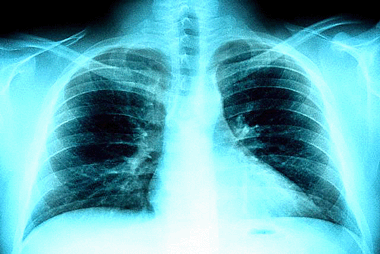

Veracruz, Ver.- El estudio “Comparación de flujo espiratorio máximo sentado y de pie en estudiantes universitarios”, realizado por los médicos Eduardo Lara Pérez, Enrique González Deschamps y Karina Lupercio Mora, del Centro de Estudios y Servicios en Salud (cess), obtuvo el segundo lugar en la I Jornada de Investigación Pediátrica del Sureste, celebrada a principios de junio pasado en la ciudad de Villahermosa, Tabasco.

De un total de 360 trabajos que se presentaron a concurso, y de 14 que fueron aceptados, la investigación realizada por el personal del cess se hizo acreedora a un segundo lugar debido a la importancia y originalidad del estudio llevado a cabo en estudiantes de la uv y porque existen pocos estudios de Flujo Espiratorio Máximo (fem) particularmente en lo que se refiere al comportamiento de acuerdo a la posición.

Cada vez que respiramos entra determinada cantidad de aire a nuestros pulmones y el flujo respiratorio es la capacidad de expulsar el aire que se encuentra en la cavidad pulmonar. La

investigación se propuso observar si esa capacidad variaba de acuerdo a la posición de pie o sentado.

La mayoría de los estudios recomiendan tomar el fem en posición de pie, pero se desconoce si existen diferencias de acuerdo a la postura. “Es fundamental –describe el estudio–, saber si estas diferencias existen, lo que nos llevaría a evaluar correctamente las condiciones pulmonares de un individuo tanto enfermo como sano”, ya que se cree que podrían darse cifras diferentes si se mide de pie o sentado.

Los médicos del cees estaban interesados en saber si efectivamente los mejores resultados se obtenían midiendo el fem de pie, por eso encuestaron a 228 universitarios (111 mujeres y 117 varones, con un promedio de 21 años de edad) a quienes que se les tomó nombre, edad, sexo, talla y fem sentados y de pie con el flujómetro Tru-Zone.

Para ello se les pidió que no realizaran ejercicios ni consumieran bebidas calientes o estimulantes media hora antes de la prueba.

El flujo respiratorio máximo es una prueba que consiste en la expulsión fuerte y rápida por la boca de una columna de aire posterior a una inspiración profunda que se mide con un flujómetro en litros por minuto y se correlaciona con el volumen respiratorio forzado del primer segundo.

Antiguamente, cuando los médicos pedían a un paciente con enfermedades respiratorias silbar o soplar una vela, estaban valorando, ordinariamente, la velocidad del fem. A partir de la creación de programas para el asma como el Gina (Global Iniciative of Asthma), se ha tratado de introducir en la práctica médica el fem como herramienta clínica.

Los resultados de la investigación efectuada por el cess indicaron que el fem es mayor en posición de pie que en posición sentado y los valores son mayores para hombres en ambas posiciones. En el total de la muestra en la posición sentados, el valor mínimo fue de 160 litros por minuto (lpm), y el máximo de 800 lpm, con promedio de 450 lpm.

Para el fem de pie, el valor mínimo fue de 170 lpm con máximo de 800 y promedio de 470, con lo que se comprueba que es mejor medir el fem en posición de pie.